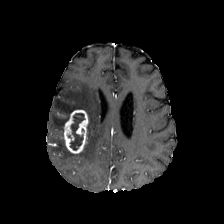

Diffusion models have shown impressive performance for generative modelling of images. In this paper, we present a novel semantic segmentation method based on diffusion models. By modifying the training and sampling scheme, we show that diffusion models can perform lesion segmentation of medical images. To generate an image specific segmentation, we train the model on the ground truth segmentation, and use the image as a prior during training and in every step during the sampling process. With the given stochastic sampling process, we can generate a distribution of segmentation masks. This property allows us to compute pixel-wise uncertainty maps of the segmentation, and allows an implicit ensemble of segmentations that increases the segmentation performance. We evaluate our method on the BRATS2020 dataset for brain tumor segmentation. Compared to state-of-the-art segmentation models, our approach yields good segmentation results and, additionally, detailed uncertainty maps.